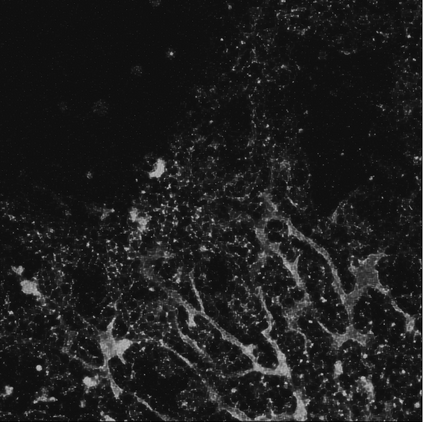

Motivated by the challenging segmentation task of pancreatic tubular networks, this paper tackles two commonly encountered problems in biomedical imaging: Topological consistency of the segmentation, and expensive or difficult annotation. Our contributions are the following: a) We propose a topological score which measures both topological and geometric consistency between the predicted and ground truth segmentations, applied to model selection and validation. b) We provide a full deep-learning methodology for this difficult noisy task on time-series image data. In our method, we first use a semisupervised U-net architecture, applicable to generic segmentation tasks, which jointly trains an autoencoder and a segmentation network. We then use tracking of loops over time to further improve the predicted topology. This semi-supervised approach allows us to utilize unannotated data to learn feature representations that generalize to test data with high variability, in spite of our annotated training data having very limited variation. Our contributions are validated on a challenging segmentation task, locating tubular structures in the fetal pancreas from noisy live imaging confocal microscopy. We show that our semi-supervised model outperforms not only fully supervised and pre-trained models but also an approach which takes topological consistency into account during training. Further, our approach achieves a mean loop score of 0.808 for detecting loops in the fetal pancreas, compared to a U-net trained with clDice with mean loop score 0.762.